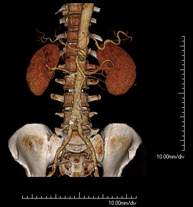

Prova diagnòstica no invasiva que consisteix en l'estudi de l'artèria aorta abdominal a través de l'obtenció d'imatges d'alta definició anatòmica mitjançant l'ús d'un equip de TC (Tomografia Computeritzada) i de contrast iodat. La qualitat de les imatges permet realitzar reconstruccions en 2D i 3D gràcies a estacions de treball especialitzades en l'estudi arterial. Està indicat en aquells pacients amb malaltia vascular (arteriosclerosi), en aneurismes d'aorta, en pacients amb dolor abdominal de possible origen vascular, en estudis prequirúrgics de lesions adjacents a l'aorta abdominal com a "mapa" vascular. La informació obtinguda de manera no invasiva és indispensable per als pacients que requereixen tractament percutani o quirúrgic. En aquells pacients que només requereixen seguiment de les lesions vasculars, aquesta tècnica és la tècnica no invasiva d'elecció juntament amb l'angio-RM. - Angio-TC Artèries renals

Prova diagnòstica no invasiva que consisteix en l'estudi de les artèries renals a través de l'obtenció d'imatges d'alta definició anatòmica mitjançant l'ús d'un equip de TC (Tomografia Computeritzada) i de contrast iodat. La qualitat de les imatges permet realitzar reconstruccions en 2D i 3D gràcies a estacions de treball especialitzades en l'estudi arterial. Està indicat en aquells pacients amb malaltia vascular (arteriosclerosi), en aneurismes d'aorta, en pacients amb dolor abdominal de possible origen vascular, en estudis prequirúrgics de lesions adjacents a l'aorta abdominal com a "mapa" vascular. La informació obtinguda de manera no invasiva és indispensable per als pacients que requereixen tractament percutani o quirúrgic. En aquells pacients que només requereixen seguiment de les lesions vasculars, aquesta tècnica és la tècnica no invasiva d'elecció juntament amb l'angio-RM. - Angio-TC Aorto-ilíac